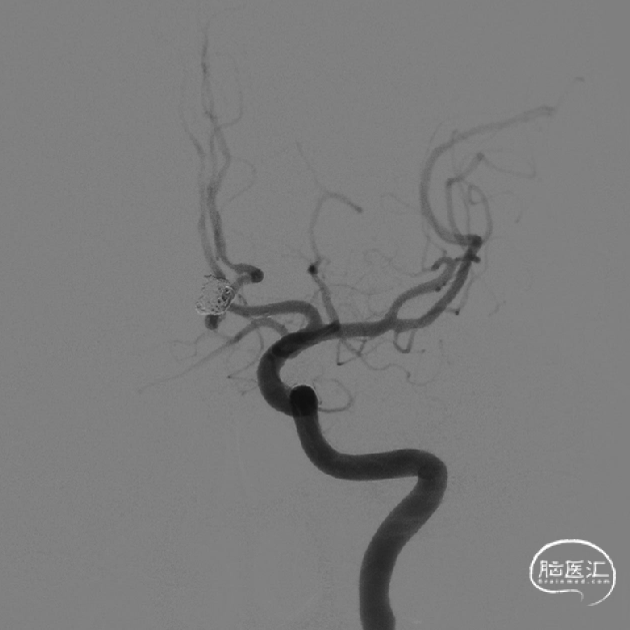

术前影像

术前DSA影像

术后影像

释放支架后继续填塞至动脉瘤不显影。双侧A1-A2显影良好。患者术后神经体检正常。